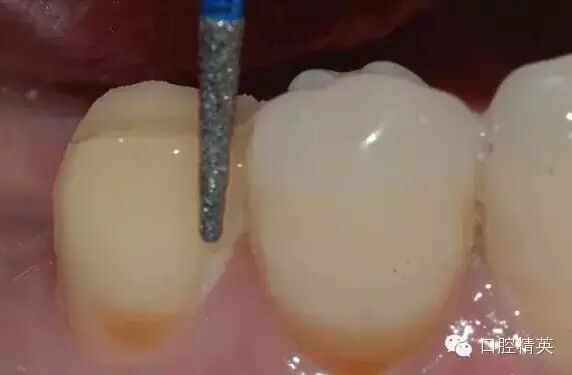

鄰面的制備,先用較細的金剛砂車針貼基牙鄰面制備,勿損傷鄰牙

鄰面制備完成后